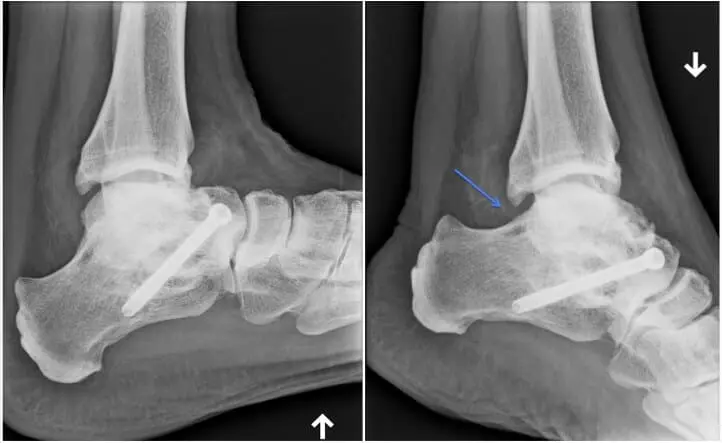

Les patients restants douloureux, en dépit de l’injection, avec des plaintes récidivantes, peuvent bénéficier d’une arthroscopie. Le nettoyage de la partie postérieure s’effectuera par deux petites incisions, qui permettront d’introduire des instruments comme la caméra et les pinces qui permettent d’enlever les tissus malades, le tout en hôpital de jour.

Suite postopératoire

Afin d’éviter un hématome, qui se développe souvent après l’opération, et risque de causer les mêmes symptômes, il est fortement recommandé de mobiliser rapidement la cheville dans les amplitudes maximales, et cela immédiatement dès le réveil. De plus, l’appui sera immédiat, sauf s’il s’agit d’une lésion cartilagineuse (6 semaines avec des béquilles).